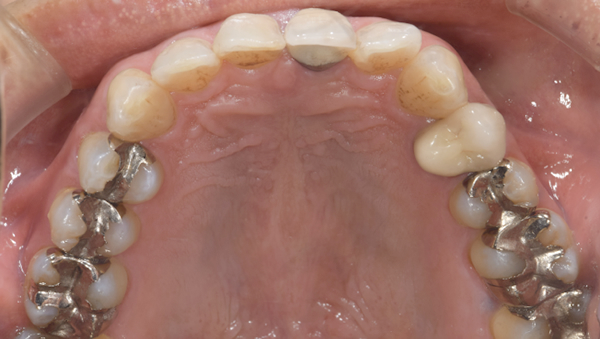

年齢・性別 40代・男性

主訴 銀歯を白くしたい

治療方針 金属を使った詰め物、被せ物を外して、セラミックでの詰め物、被せ物にやりかえたいというご要望がありました。

奥歯はほとんどの歯に詰め物が入っていましたので、まずは奥歯から噛み合わせをきちんと作ってから前歯の被せ物をやりかえていく方針としました。

また、左下の奥から1番目の歯は虫歯が大きいことをレントゲンで確認できており、神経を取り除かねばならない可能性が高いことを説明してから、治療をおこなっていきました。

治療内容 左下の奥から2番目の歯は、やはり神経を取り除く必要がありました。その他の奥歯の部位は詰め物のやり変えのみですみました。 前歯は金属の土台(メタルコア)も取り除き、セラミックとジルコニアでできた被せ物を入れていきました。

治療費 合計:903,100円

(内訳)

セラミックインレー:55,000円×11本

ファイバーコア:16,500円

仮歯:3,300円×2本

ジルコニアボンドクラウン:165,000円

ジルコニアステインクラウン:110,000円

治療期間 4ヶ月

治療のリスク・副作用 詰め物を入れた後も冷たいものなどで染みることがあります。 今回のケースのように、銀歯の下では虫歯になっていることがおおく、神経を取り除かねばならないことが多々あります。

治療前

治療前 パノラマレントゲン写真

担当医師所見:

銀歯の詰め物の下で虫歯があり、神経を取り除く必要が高いことがわかります。

銀歯が多々奥歯につめられており、噛み合わせもきちんと見ていく必要があります。

奥歯の詰め物の治療終了後

奥歯の治療が終わったところです。前歯の治療に行く前に、噛み合わせをしっかり確認します。

治療後

全ての治療終了後

前歯の治療が終わったところです。前歯は全く違和感がなく入っています。

全体の治療前後

銀歯の主張がなくなり、とても自然になりました。見た目もそうですが、雰囲気や第一印象もかなり変わりました。